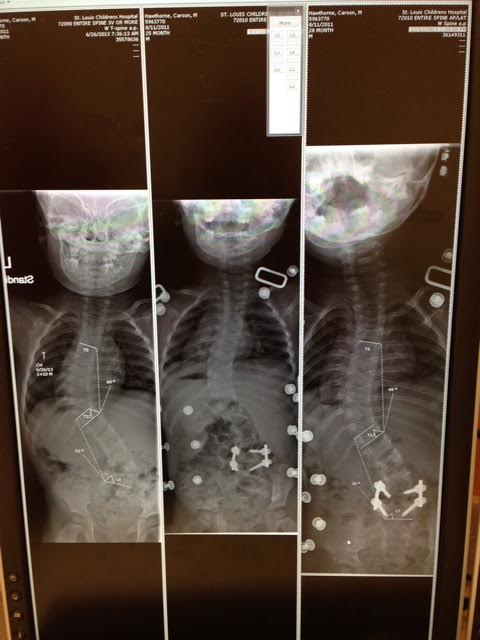

the carseat and in a high back high chair for meals. For 11 more weeks he would have the one leg cuff on his brace. During this post-op time my husband and I started to do more research on what our next step should be. We ran across Mehta casting before his surgery, but always read that congenital cases weren’t being casted. Now that his hemivertebrae was removed, we wondered if he would be a candidate for casting since his large thoracic curve had to be addressed. Our surgeon in St Louis recommended more bracing until old enough for growing rods. We brought up casting to him at that first post-op appointment and he was onboard with our plan to get other opinions, specifically from those who are Mehta trained, since he doesn’t cast. We had a trip planned to visit family in Chicago in January 2014. We rearranged our flights and days and made appointments with Chicago Shriners and Cincinnati Childrens. We also made an appointment for a month later with our surgeons partner in St Louis.

Our first appointment was with Chicago Shriners. We were hit with some very hard news that Carson most likely had another congenital vertebrae defect, a bar from T10-T12. We were told that his disc spaces in his thoracic spine weren’t normal, but never that he had another boney abnormality. Chicago said that he was not a candidate for casting.

We drove to Cincinnati a week later. The doctor agreed that Carson did most likely have a bar. He said casting on congenital issues was not often done, but it could delay the progression of his curve, buying us very valuable growth time. We had a feeling Cincinnati would be the place for us, even before meeting them and after that appointment we were sold. My husband and I were so extremely happy with them. In fact, the nurse had even given us a casting day even before our appointment and said we could cancel if we needed but this way he was on the schedule and could start soon. So we ended up canceling our 3rd casting opinion in St Louis, went home and started booking flights for just a month later to get Carson first cast.

Casting has successfully held Carson’s thoracic curve at about 53 degrees. That’s a huge success in our minds. Our doctor believes that if we would have just braced him all this time that his curve would have progressed, and we also agree. Our future plan is to take it one step at a time. We will cast for as long as the benefits out way the risks.